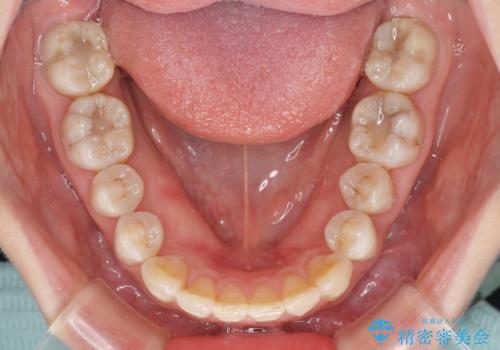

話しにくいオープンバイト インビザラインによる矯正治療

- 前歯の上下スペースによる話しにくさを気にして来院された患者様です。

インビザラインにより上下の前歯の隙間を閉じていくこととしました。

上下の奥歯を圧下させるようにすることで、前歯を接触させるように計画しました。

隙間に舌が入り込むことが話しにくさに繋がっていたため、舌の筋肉のトレーニングも並行して行い、話しにくさの改善と後戻りの抑制を図りました。